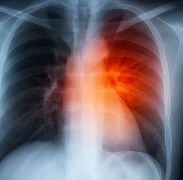

- 흉부 X-ray: 폐에 물이 차 있는지 확인.